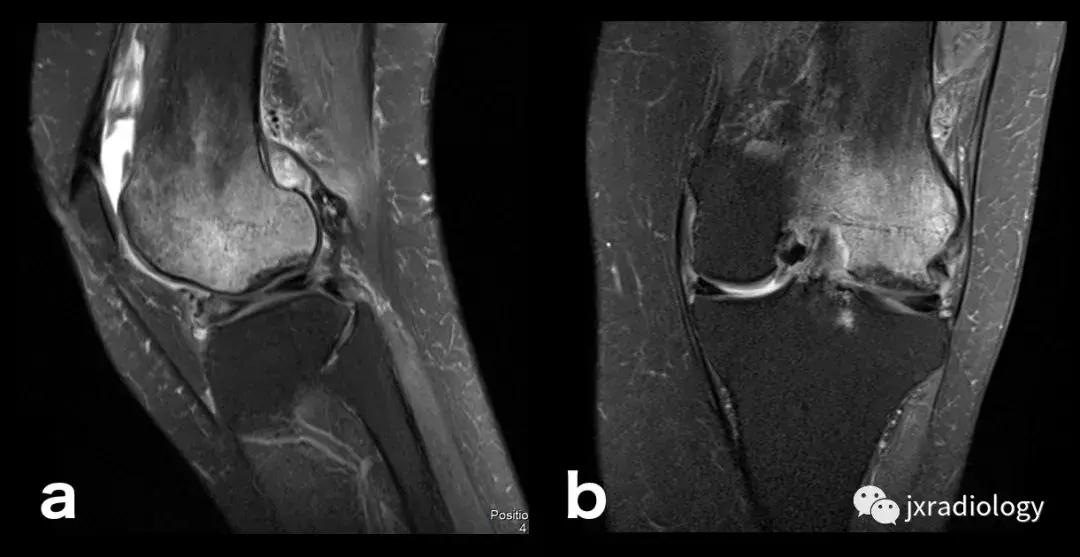

图25:短暂性骨髓水肿综合征(短暂性骨质疏松症):30岁女性急性膝部疼痛的矢状位FS-PDWI MR影像显示骨髓水肿,涉及非负重区域股骨外侧髁骨髓水肿在1年内几乎完全自发消退。短暂性骨髓水肿综合征是自限性病变,其表现为与MRI研究中的骨髓水肿证据相关的关节痛。 其病因仍不确定。

图26:局限性游走性骨质疏松症(具有位置变化的短暂性骨髓水肿综合征)(连续冠状PD-FS-WI):在一些情况下,在连续MRI上看到骨髓水肿的位置变化,这被称为局限性游走性骨质疏松症(RMO);尽管可以自愈的短暂性骨髓水肿综合征的情况更为常见,但可以在一小部分病例中转移到不同的关节,或者(甚至更罕见)转移到同一关节内的不同部位(关节内转移) ,如关于该患者所见。在这个关节内RMO病例中,没有创伤史,水肿始于股骨内侧髁,3个月后发现转移到外侧髁。